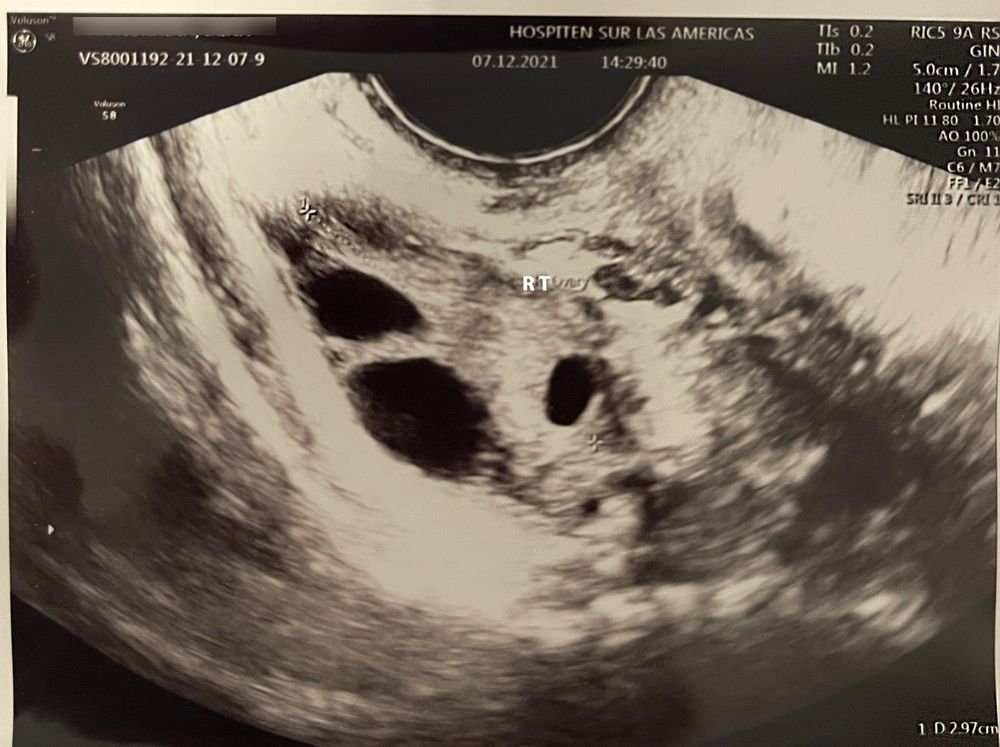

Узи яичников, овуляция

Работаем над зачатием ребеночка третий цикл, прошлый месяц фолликулы были недозревшие, без овуляции. в этом цикле тоже загадка, была овуляция или нет. Видно ли, что зреет доминантный ф?

Дата этого узи 07.12.21 (это 8 день цикла). Есть ли надежда что овуля все-таки была? Врач пока не хочет отслеживать этапность роста фолликулов, сказал сдать сначала анализы и потом будет смотреть, что дальше делать.

Правый яичник